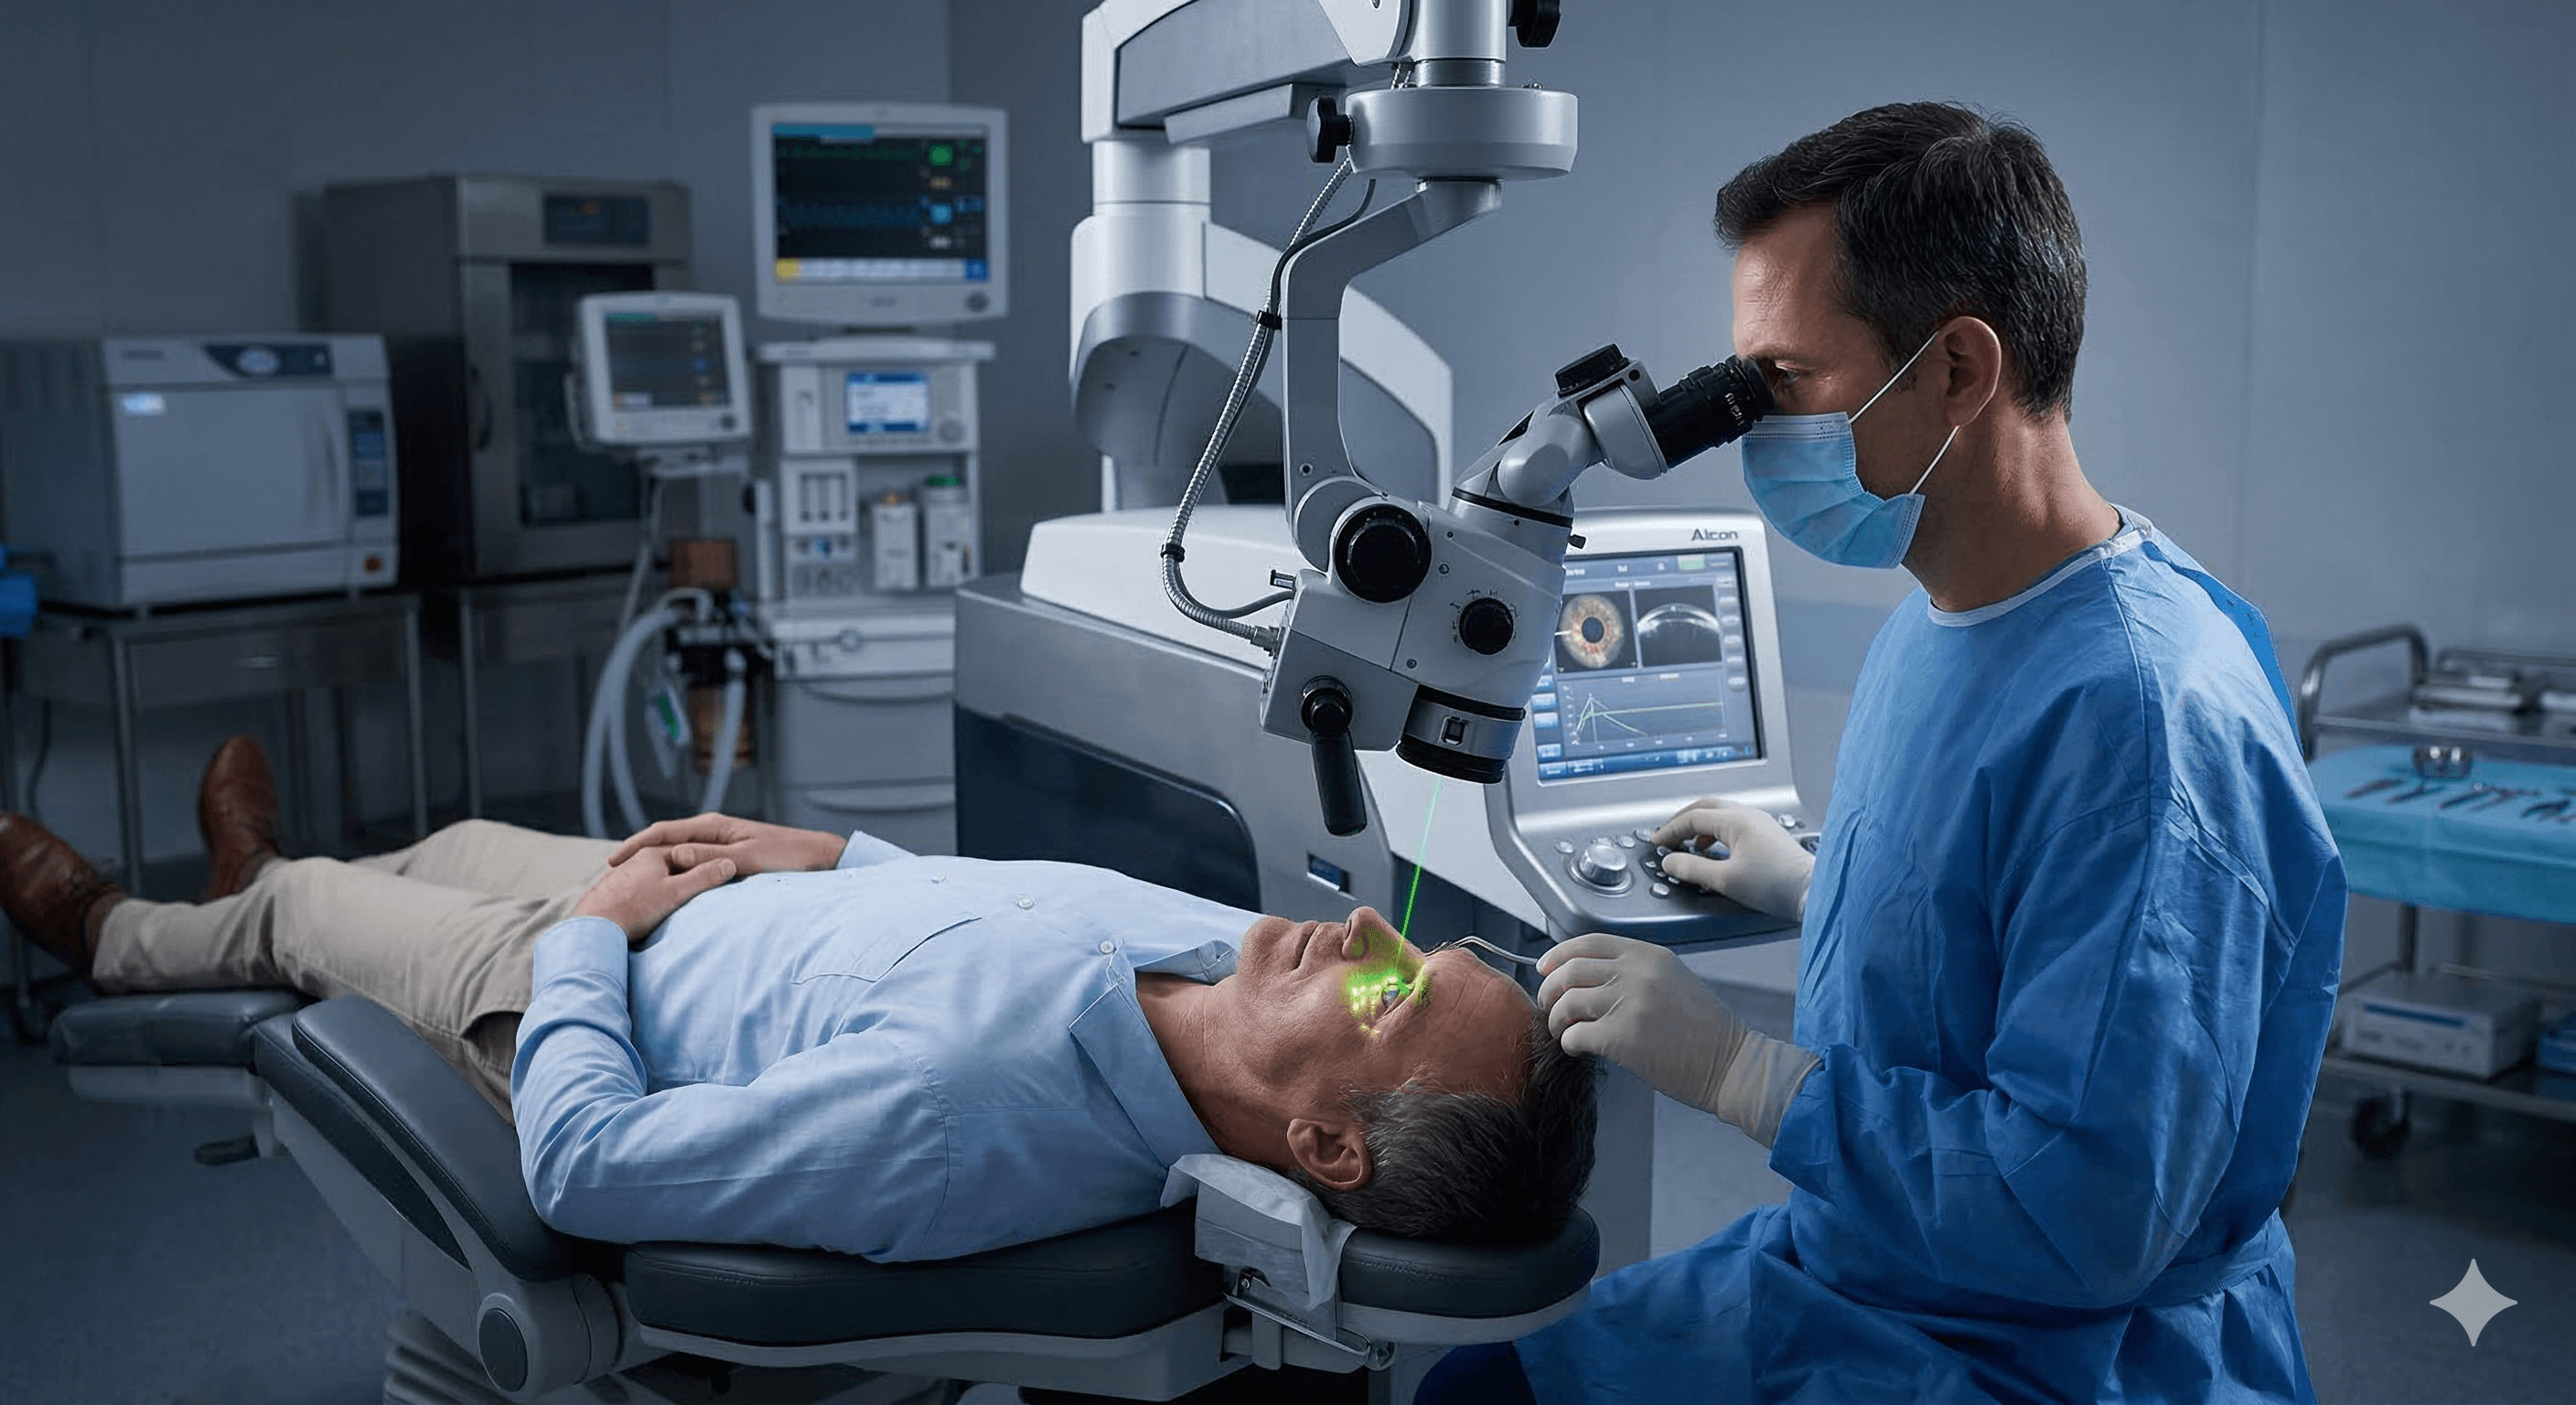

Cirugía de Catarata

Microcirugía Ocular

Inversión en tu salud visual

Obtén un diagnóstico preciso y un tratamiento personalizado con tecnología de vanguardia para el cuidado de tus ojos.